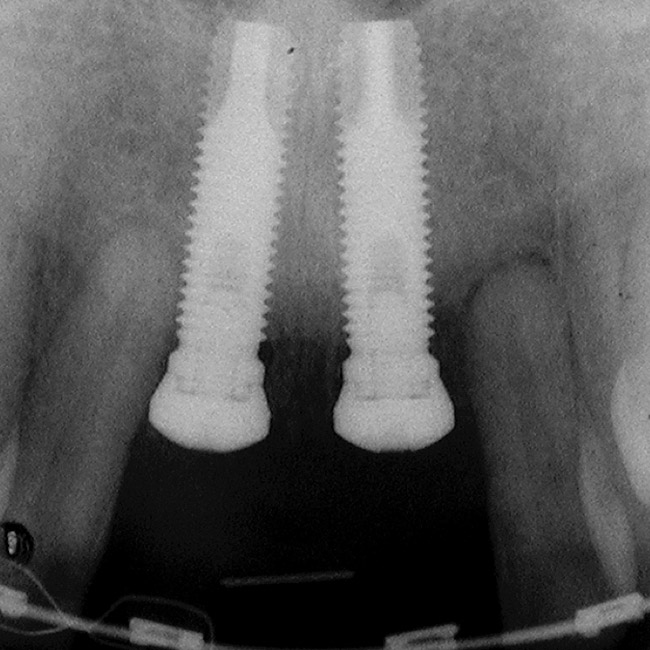

Figure 7  Because the interproximal crestal bone was maintained and the soft tissue supported at the time of tooth removal, an excellent interimplant papilla exists.

Figure 7

Figure 8  Maintenance of interproximal crestal bone following final restoration placement.

Figure 8